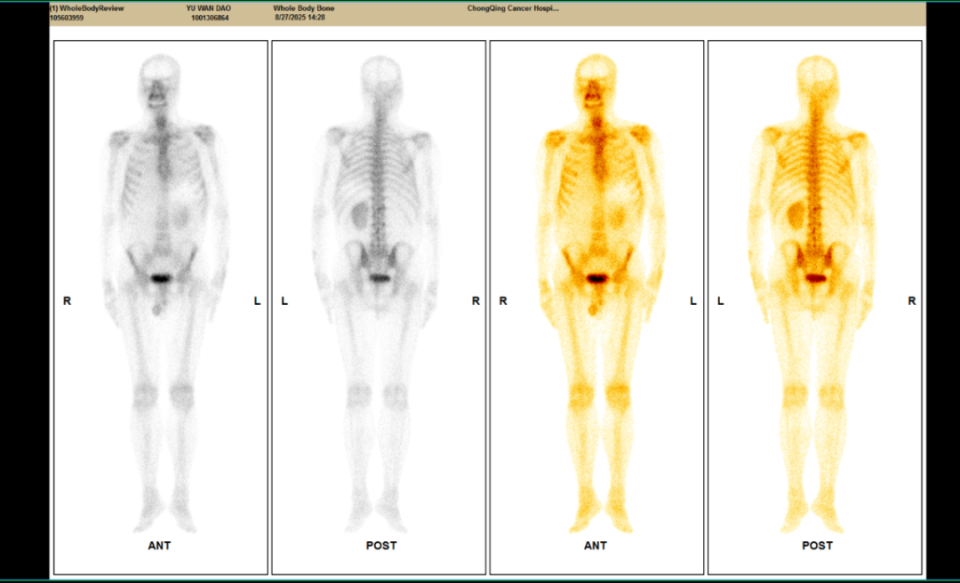

△2023年2月患者基线时CT(左)与2024年4月时CT(右)检查所见对比

患者2025-02-13起转为呋喹替尼单药治疗,剂量及用法同前,共治疗9个周期,后患者于2025-08-21复查CT及SPECT骨扫描,靶病灶疗效评价仍维持PR,但检查同时示胸12椎体存在转移可能,综合考虑疗效为疾病进展(PD),遂终止呋喹替尼治疗。

△2025年8月疗效评估时患者CT检查(右)较基线(左)对比

△2025年8月疗效评估时患者CT检查(上)及SPECT骨扫描(下)提示新发胸椎转移